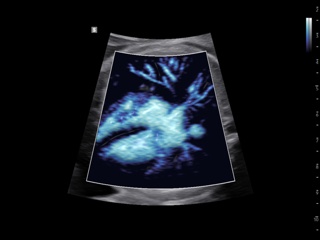

Atlas of ultrasound images - obsterics

In the section "Оbsterics" of atlas the results of ultrasonic examinations of pregnant women with different durations of gestation are represented. Here you can see images of internally organs, cerebrum, cordis and the sex of the fetus, the sonograms of multiple pregnancy, the blood flow in placenta and umbilical cord, defects of fetal`s development, etc.